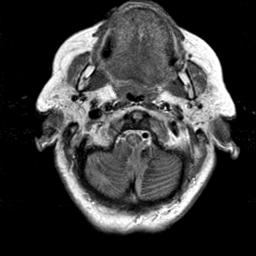

To demonstrate the effectiveness and efficiency of the proposed image fusion method , we conduct a set of comparative experiments on three image datasets. The first is composed by 8 pairs of multi-modal medical images and the second one contains 15 pairs of multi-focus gray or color natural images. These two datasets are often used in many related papers and some examples are shown in Figure 3(a) and Figure 3(b). The third one is a new multi-focus cervical cell image dataset collected by ourselves, which consists of 15 groups of color images and each group contains a series of multi-focus cervix cell images with size of or , etc. Some source examples are shown in Figure 3(c). Our source code implemented in C++ along with the new multi-focus cervical cell image dataset is available online.

We first evaluate the performance of the proposed method under varying total number of octaves and number of layers sampled per octave. The fused images of a pair of multi-modal medical images with different and are shown in Figure 4. In this example, on the one hand, when only 1 or 2 octaves are involved in constructing the DoG pyramid, the fused images fail to keep the integrity information of large size objects (e.g. eyeballs), while by increasing the value of , the integrity information of eyeballs is preserved. On the other hand, although not as significant as the increase of octave numbers , the fused image can contain more details by the increase of layer numbers . The corresponding objective quality metrics are shown in Figure 5. As shown in Figure 5(a), most of the metric values are improved as the number of octaves increases with the fixed layer numbers 3 in the global tendency and each of them tends to be stable when the number of octaves is 5. To get a relatively good quality from Figure 5(b), we can notice that some of the metric values can get a good performance when the number of layers is 3, such as the MI, SSIM, QI and VIF, though there are only a little change of all the metric values by increasing the number of layers with the fixed octave numbers 5. Because it will result in more computation burden with the increase of the value and , and for different kinds of source images, there are different performance with the diverse parameter settings. To get a trade-off between them in our experiments, we set for the multi-modal dataset, for the natural datasets and for the multi-focus cell dataset, respectively.

Figure 6 shows the fused images obtained by different methods with the multi-modal source images shown in Figure 3(a). As shown in these figures, the proposed method can produce images which preserve the complementary information of different source images well. Moreover, due to the scale-invariant structure saliency selection, our method can keep the integrity information of large size objects and the visual details simultaneously. Although the fused image generated by other methods can also capture the details to some extent, all of them fail to keep the integrity information of large size objects such as the eyeballs. Furthermore, from Figure 6(k)-6(t), the DTCWT, GFF, IM and NSCT methods may decrease the brightness and contrast while the proposed method can preserve these features and details without producing visible artifacts and brightness distortions.